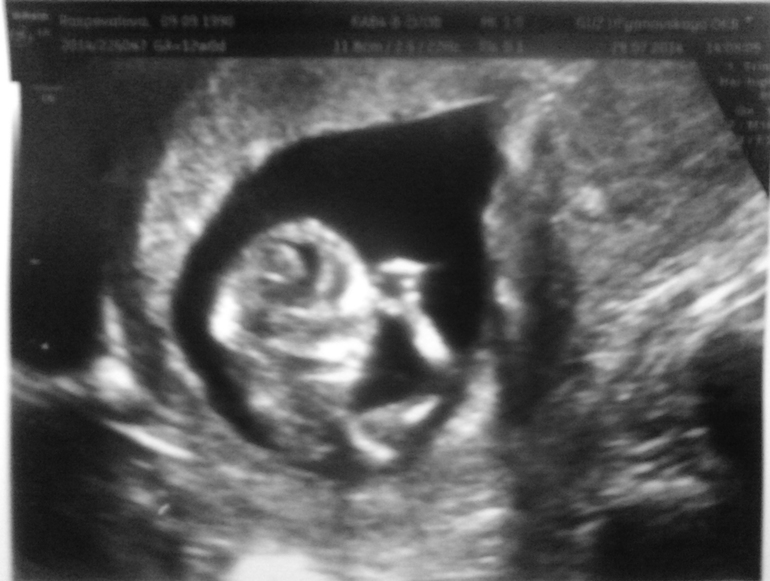

Второе узи

Девочки!!)) вот и мы были на узи!)) Наш писюнчик куда-то делся и врач говорит, что видит девочку:))))))))))))

Очень неожиданно, вот такие дела!)) А мы то уже настраивались на пацана по первому узи)

Главное что все-все в норме! Наверное эта девочка очень желает появиться на свет, все точно соответствует сроку!:)